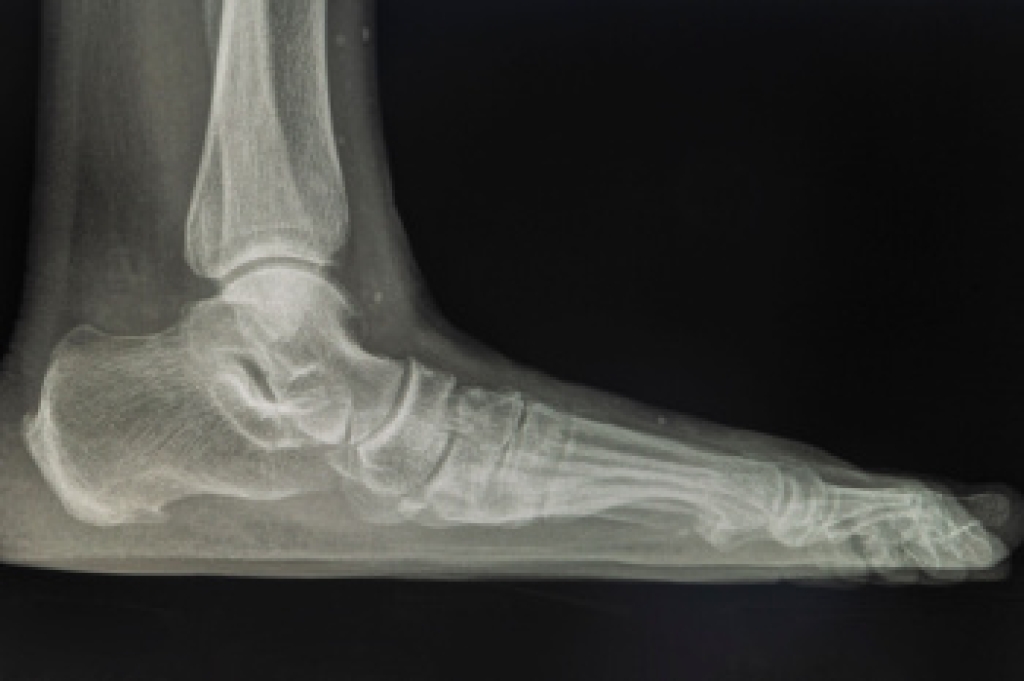

Foot pronation is the natural inward and outward movement of the foot while walking or running. In some cases, it can lead to over-pronation, where the foot excessively rolls inward, which affects gait and weight distribution. Overpronation may begin in childhood as a result of underdeveloped arches, or develop in adulthood due to arch collapse. Causes include genetics, foot deformities, and injuries. Obesity, and conditions like diabetes or arthritis, are other factors in developing pronation problems. Symptoms include pain, swelling, and related foot disorders such as plantar fasciitis or shin splints. Diagnosis involves examination, gait analysis, and imaging tests conducted by a podiatrist. If you have developed signs of overpronation, it is suggested that you make an appointment with a podiatrist for an exam and treatment options that are best for you.

Podiatric biomechanics is a particular sector of specialty podiatry with licensed practitioners who are trained to diagnose and treat conditions affecting the foot, ankle and lower leg. Biomechanics deals with the forces that act against the body, causing an interference with the biological structures. It focuses on the movement of the ankle, the foot and the forces that interact with them.